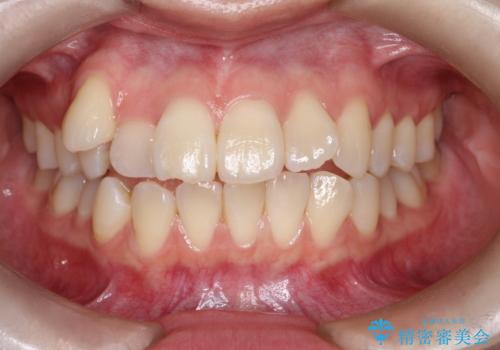

50代女性 八重歯を矯正治療 歯並びの中等度のがたつき